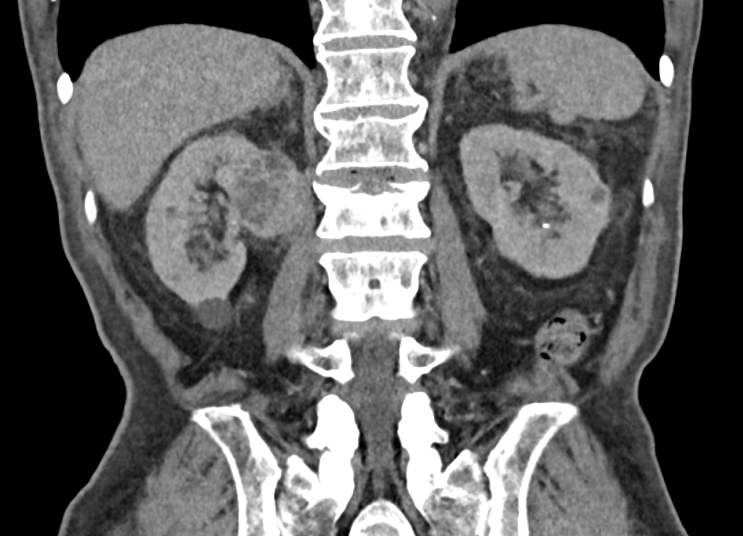

신장암 초음파 및 CT 케이스 2월 5, 2026 작성자: lupin21kr 관련 포스팅 : 췌관 확장 (Main pancreatic duct dilatation) 혈액검사에서 염소 (chloride, Cl)를 체크하는 이유 건강검진 결과지 해석 잘못된 사례 피검사로 암수치를 확인한다. 암표지자 종양표지자의 종류와 진실 8월 31일 부터 코로나 검사비용 자비로 부담해야 한다?